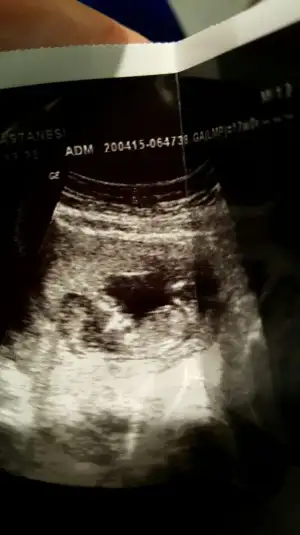

Kızlar ben yeni üyeyim.bir kızım var,ikinciye hamileyim.12+1günlük ultrason görüntüsünü yüklüyorum.bana da yorum yapar mısıniz?dr bacakları kapalı,göremedim.bu halde tahminde bulunursam kız gibi dedi.bu haftalarda yanılma payı çok olur diye yorum yapmak istemedi,ben ısrar edince kız gibi dedi.bacak arası kapalı olunca böyle düşündügünü söyledi.

benim bebişim içinde tahmin de bulunur musunuz?yukarıda ultrason görüntüsünü yükledim.4boyutlu görüntüsünü de yüklüyorum.15.hafta da net bişey söyleriz dedi dr.

Eklentiler

Orkidecim,bir yorum da benim bebişime yapabilir misin?burda ki görüntülere bakınca ben kıza benzettim.2hafta sonra dr gidecem.kızlar sizlerden yorum bekliyorum